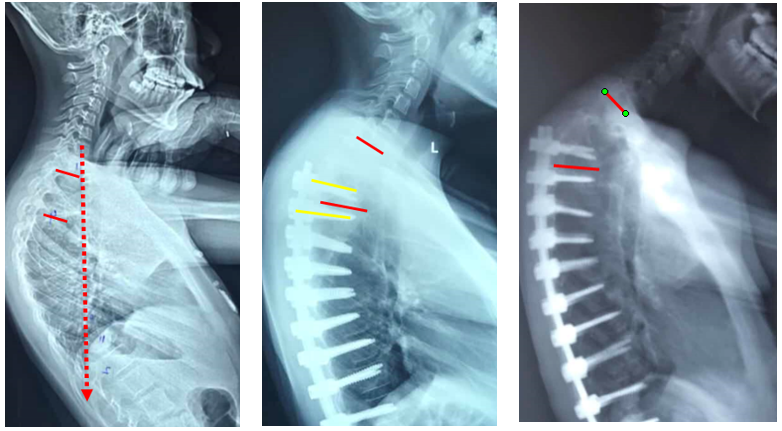

(2)上固定椎在交界区或存在交界性后凸

图6 长节段融合固定上固定椎(UIV)选择在胸10-12胸腰椎交界区是PJK的风险因素之一

图18 固定近端交界性后凸角>5°

A:术前固定近端交界性后凸角>5°;B:上固定椎未跨过此区域;C:术后随访出现PJK

Ø 颈7铅垂线距离UIV太远

图19 颈7铅垂线距离UIV太远